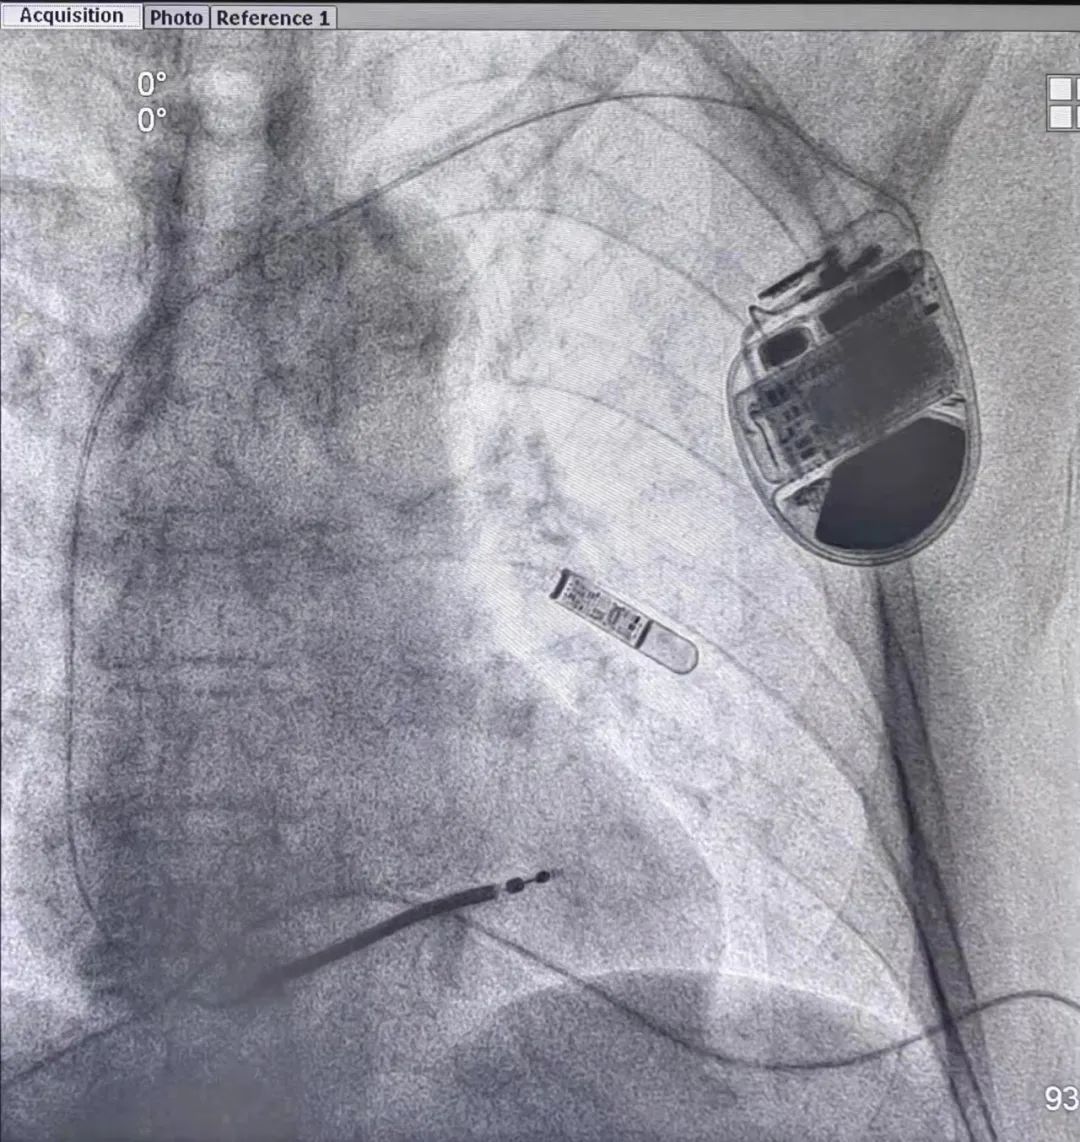

图片

陈样新教授团队为刘伯成功植入兼容3.0T MRI的ICD

入院后常规检查未见异常,冠脉原支架部位也完好无损,也没有心肌损害等其他因素。最终,老伯晕厥的“元凶”被抓住,正是险恶的室性心动过速。为了有效预防刘伯晕厥再发,降低发生心脏性猝死的风险,陈样新教授为刘伯植入了兼容3.0T核磁共振的ICD。

导致刘伯发生晕厥的室性心动过速,是一种最常见的严重威胁生命安全的恶性心律失常,也是导致患者心源性猝死的最重要原因之一。陈样新介绍,植入术心律转复除颤器(ICD)是目前预防心脏性猝死最有效的手段,可以在患者发生室速、室颤以及心脏停搏时进行第一时间的自动识别,并自动放电、起搏治疗,及时挽救患者生命,堪称“移动救护车”。

不过,传统ICD植入后患者无法进行核磁共振检查,但是刘伯已经81岁高龄,又合并有其他慢性疾病,未来有需要进行磁共振检查的可能。如果在几年前碰到这样的问题,会让临床医生陷入两难境地:不装ICD,患者将承受心源性猝死的极高风险;安装ICD,患者将失去接受MRI检查的资格。而如今这个问题已经有了两全的解决方案——兼容磁共振检查的ICD。陈样新教授为刘伯植入的就是最新兼容3.0T磁共振的ICD,该院也是国内首批使用这项新技术的医院。